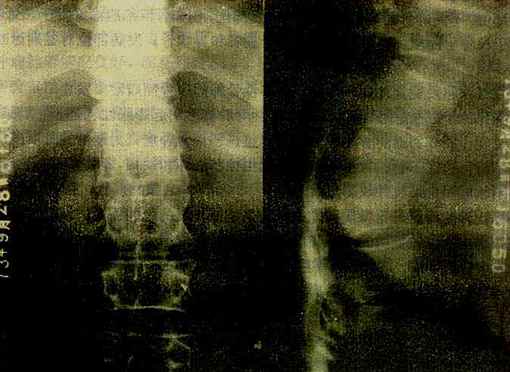

图2-1-22 脊椎结核

胸12与腰1椎体破坏、融合,两椎体间不见椎间隙,于该处有后突变形,

于右侧可见腰大肌脓肿,并有钙化